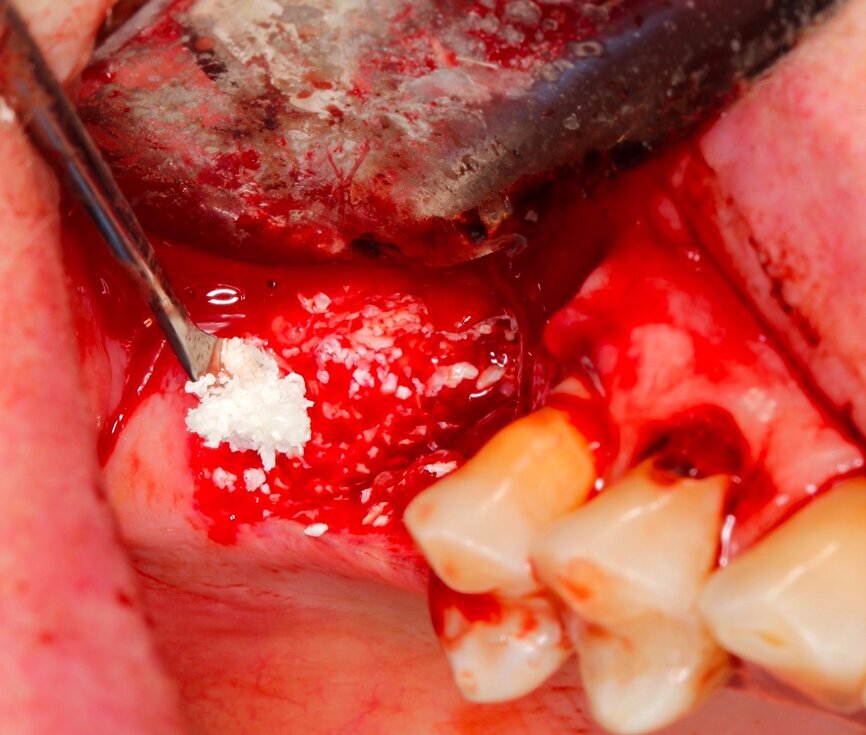

Fig. 11 Figura 11

1. Relleno del defecto con biomaterial: "Técnica de Sandwich".

• 1a Capa: hueso autólogo o hueso particulado de reabsorción rápida.

• 2da Capa: hueso particulado de reabsorción lenta.

1. Recubrimiento de la zona regenerada con membrana reabsorbible, adaptándola y extendiéndose 2 mm por fuera del defecto.